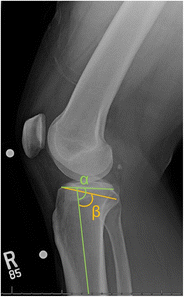

Purpose of review: The purposes of this review are to (1) describe the anatomic and biomechanical rationale for high tibial osteotomy (HTO) in the setting of posterior cruciate ligament (PCL) deficiency, (2) review the indications for concomitant HTO and PCL reconstruction, (3) provide guidance for the clinical assessment of the patient with suspected PCL deficiency, and (4) summarize the key surgical steps necessary to attain the appropriate sagittal and coronal plane corrections.

Recent findings: The preponderance of available biomechanical data pertaining to the PCL-deficient knee suggests that an increased proximal tibial slope limits posterior tibial translation under axial compressive loads. Moreover, recent clinical data has demonstrated that decreased proximal tibial slope may exacerbate residual anterior-posterior laxity and jeopardize the durability of PCL reconstruction. Thus, in the setting of PCL deficiency, an HTO that increases the posterior tibial slope may be advisable. HTO may be an important treatment adjunct in the surgical management of PCL deficiency. In the setting of chronic injuries and varus malalignment, HTO should be considered in order to ensure a durable ligamentous reconstruction and forestall the progression of secondary osteoarthritis.